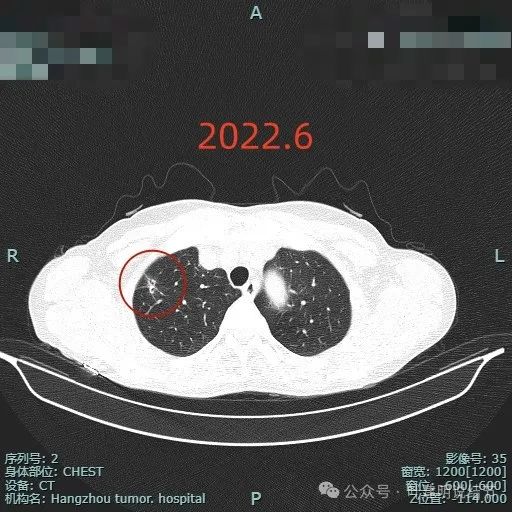

2022年6月此灶实性成分占比增多,毛刺锐利而且较前更明显了。